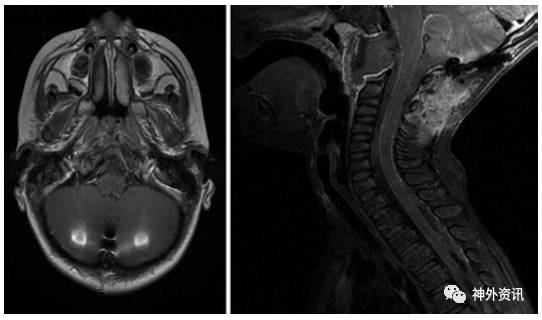

5岁男性患儿,诊断为斜坡脊索瘤(图1)。5年前行经口入路完全切除肿瘤(图2),术后进行质子束放疗。病理学检查报告为典型的脊索瘤,免疫组化提示角蛋白强阳性、上皮膜抗原强阳性、S-100免疫反应阴性和MIB-1标记指数为10%(图3)。术后因脑脊液漏反复出现脑膜炎,给予抗生素治疗后好转。接着继发交通性脑积水,通过脑脊液VP分流术降颅内压。术后5年发现肺部结节(图4),手术活检提示为低分化的脊索瘤,免疫组化结果和原发部位脊索瘤相似,即角蛋白强阳性和上皮膜抗原强阳性(图5),表明斜坡脊索瘤颅外转移。随后相继发生胸壁和颅骨转移。由于大部分脊索瘤mTOR通路激活,所以给患者使用伊马替尼联合雷帕霉素化疗后,肿瘤缩小,疼痛有所减轻。但是,9月后出现额部头皮肿物,并导致附近的VP分流管周围皮肤破溃。遂行头皮肿物切除和皮瓣转移术,以防止分流管暴露。免疫组化提示PD-L1高表达,即行PD-L1单抗治疗,胸痛明显缓解。6月后又出现新发的肺部转移灶,疼痛明显。免疫组化和基因检测为INI-1缺失,应用EZH2进行晚期解救治疗,疗效尚待评价。

图1. MRI提示斜坡区一肿物。A.TI加权平扫;C.T2加权平扫;B和D.T1加权增强。